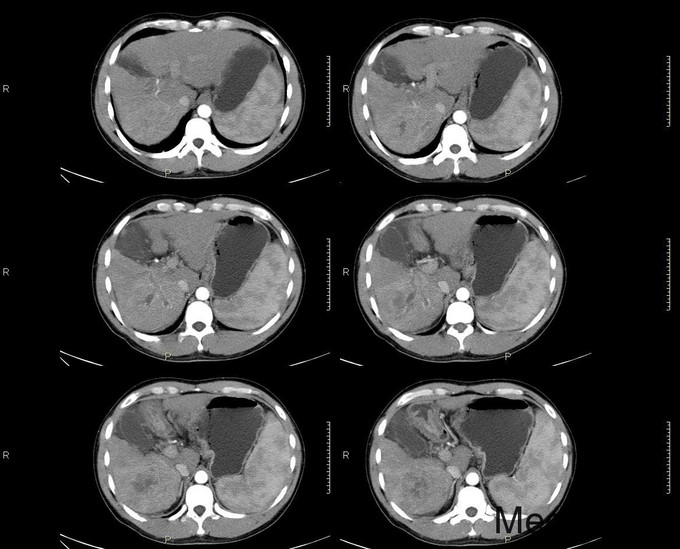

主诉:反复乏力、纳差2月余。身目黄染1月余。 病史:患者中老年男性,2月前出现乏力、纳差,查乙肝两对半示大三阳,上腹部CT示肝硬化,予护肝等治疗后好转出院。1月前天前出现身目黄染,伴瘙痒,再次入院。 既往史:患者有肝癌家族史(父亲肝癌去世)

查体:慢性肝病体征,肝掌阳性,蜘蛛痣阳性,胸前毛细血管扩张,腹水征阳性,肝脾肋下可触及。 辅查:生化:谷草146,谷丙110,总胆184,直胆114,白蛋白38,凝血四项:PT17.9s,PTA56。 CA-125: 600,CA-199:54.13,AFP:98.73。 肝彩:1、肝硬化,肝左叶可见高回声团。 上腹部CT: 肝癌、肝硬化、脾大

诊断:1、原发性肝癌;2、乙肝肝硬化 1、常规护肝退黄降酶,输血浆,护胃制酸等对症支持治疗 2、转肝脏外科。